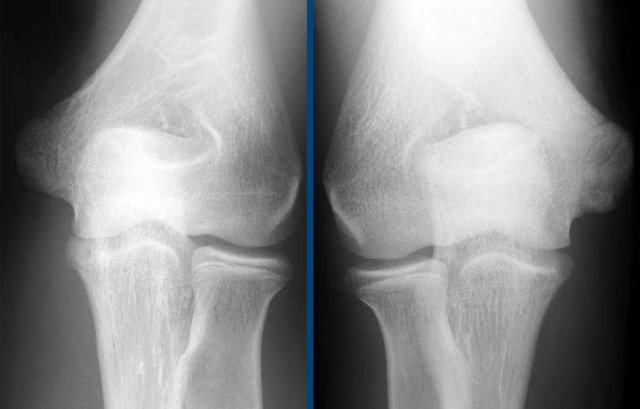

The radiograph is of a 15 year old baseball player with 4 year history of elbow pain and a recent episode of locking.

There is a focal lucency in the capitellum and some fragmntation.

This is typical for a osteochondral lesion of the capitellum and the locking is probably the result of loose bodies.

Continue with the MR...

Here another case in a 20 year old gymnast.

Again there is lucency on the radiograph.